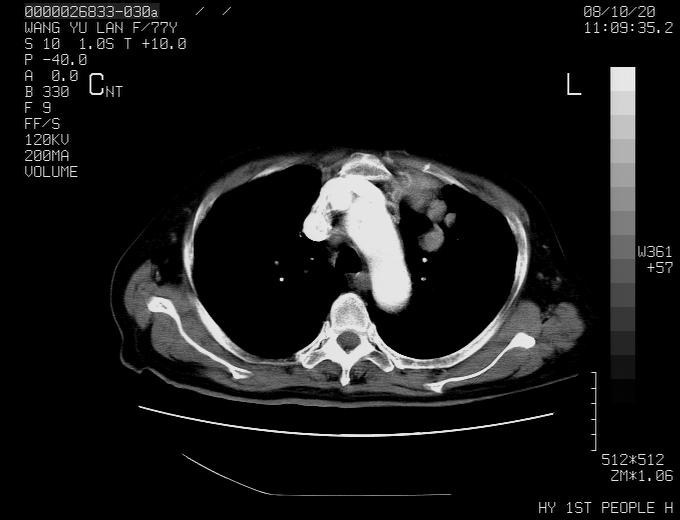

女性,77岁,胸部疼痛半月。左上肺团块影,本人考虑血管畸形,请分析

非常典型的avm(谢谢楼主,收藏了)

动脉期未见大血管同步强化,首先考虑周围型肺癌

动脉期病灶近中线侧可见星芒状与大血管同等强化密度,支持考虑血管畸形伴血栓形成,动脉期不曲型,不除外周围型肺癌

1、考虑avm可能性大。2、纵隔有肿大淋巴结,左肺上叶有炎性病变,不排除肺癌并转移可能。